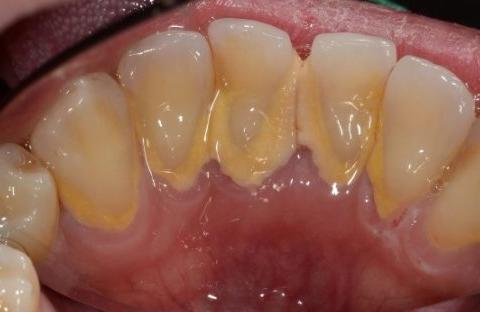

牙石是一种附着在牙齿表面的黄色钙化物。我们的口腔并不是无菌状态,口腔里有无数细菌,我们每天吃的食物如果没有及时清洁,食物残渣在口腔缝隙里超过五分钟,就会形成牙菌斑。牙菌斑粘附在牙齿表面不容易被冲走,再得不到及时的清洁,牙菌斑和食物残渣就会在唾液的浸泡下“钙化”,形成牙结石。所以我们应该在饭后12h内用牙线或牙刷清除牙菌斑。牙结石一旦形成,并越积越厚,普通刷牙就很难去除了。

牙结石就像我们口腔里的一个小型垃圾场,如果不及时清理,就会损伤牙釉质,造成牙龈出血,引起牙周疾病和口臭等。牙结石得不到及时的清除,还会造成骨骼退化甚至是心脏病。